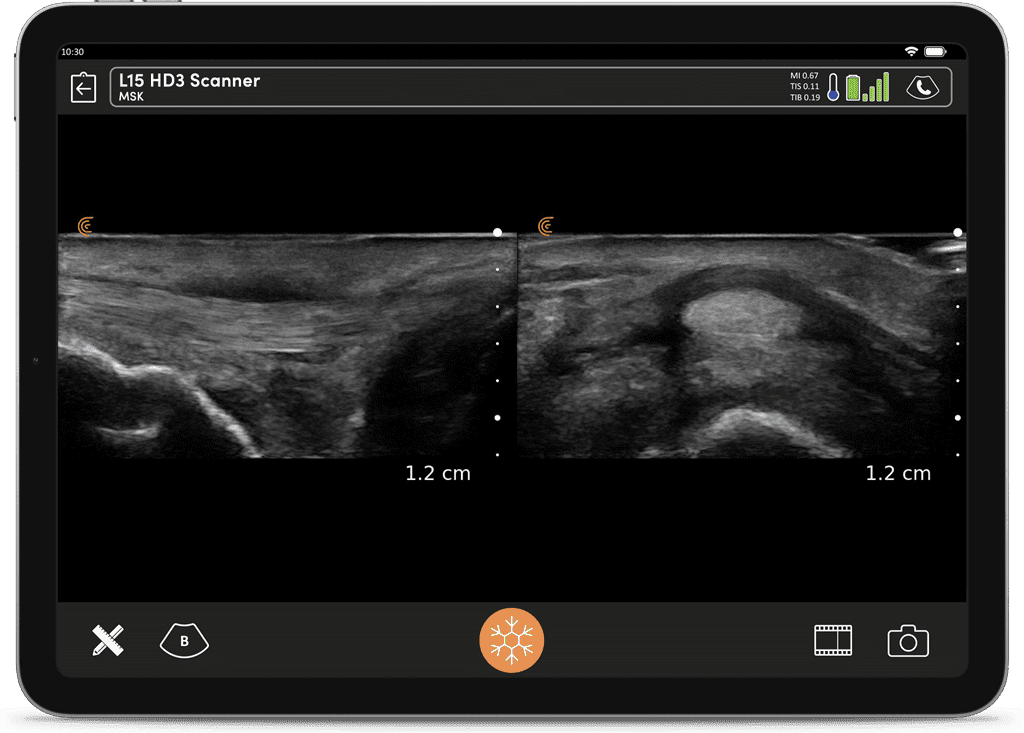

Imagerie Obstétricale Optimisée

I feel more confident with my ultrasound exams since I’ve started using OB AI. I love how the AI makes the app light up when things are perfectly lined up – I can see this really helping both seasoned clinicians and those who are starting their ultrasound journey.